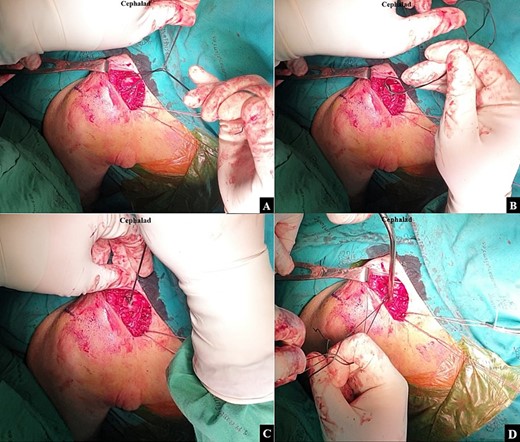

The surgical intervention was performed using a standard technique until exposing the coracoid base. An Ethibond No.2 suture was passed beneath the coracoid base from the medial side to the lateral side, and was then exchanged for a shuttle loop. An Ethibond No.5 suture was then folded, and the looped end passed beneath the coracoid base using the shuttle suture technique (Fig. 2). The operative field was adjusted to optimize visualization of the clavicle, and the clavicular fascia was incised along the clavicular bone to allow distinct demarcation of both the anterior and posterior clavicular borders. A right-angle clamp was utilized to create a tunnel from the coracoid base to the anterior clavicular border of the proximal fragment (Fig. 3A). The looped end of the Ethibond No.5 was then passed from the coracoid base to the anterior clavicular border of the proximal fragment using the right-angle clamp (Fig. 3B). The same technique was employed to create a second soft tissue tunnel from the coracoid base to the posterior clavicular border of the proximal fragment (Fig. 4A). The open end of the Ethibond No.5 was then passed from the coracoid base to the posterior clavicular border of the proximal fragment using the right-angle clamp (Fig. 4B). After a doubled-suture of the Ethibond No.5 was passed around the coracoid base and proximal fragment of the clavicle, a single square knot was thrown (Fig. 5A). The two open ends of the Ethibond No.5 were passed through the loop (Fig. 5B). The knot was dressed and slid down by pulling the two open ends of the Ethibond No.5 (Fig. 5C). The Nice knot was slowly tightened to incrementally slide the proximal fragment to the correct alignment with the distal fragment for the closed reduction (Fig. 5D) [1]. The fracture alignment was continually checked under fluoroscopy, and when a good alignment was achieved, the Nice knot was firmly tied.

After the doubled-suture of Ethibond No.5 was passed around the coracoid base and proximal fragment of the clavicle, (A) a single square knot was thrown. (B) The two open ends of the Ethibond No.5 were passed through the loop. (C) The knot was dressed and slid down by pulling the two open ends of the Ethibond No.5. (D) A Nice knot was slowly tightened to incrementally slide the proximal fragment to the correct alignment with the distal fragment for the closed reduction.